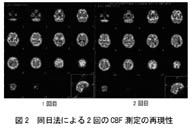

a)より正確な病態の把握のために、MRIとのfusion画像の作成の必要性が高まると思われる。これによってMRIのすぐれた解剖情報と核医学の機能情報をドッキングする事ができるからである。ただし現状のソフトウェアは機能的にも価格の面からも不十分である。また脳血流シンチでは、まさに病態の正確な把握のための定量測定が不可欠となると言える。さらに脳循環予備能としてダイアモックスに対する反応性を測定する場合に、従来は2日に分けて検査を行っていたが、今後はコストや患者の利便を考慮して同日法で行われるようになると予測される。信頼できうる方法が確立されれば、患者の状態の変化なしに評価できるため、むしろ2日法より正確であろう。図2に我々の方法(仮にsequential dynamic methodとする)で求めた2回のCBF測定の安定性を示す。ダイアモックス負荷を行わない場合の2回の半脳平均血流値の変動は数パーセント以内であった。次いで